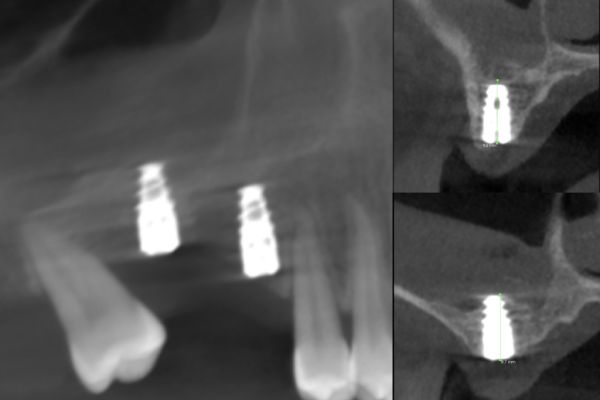

El equipo de Jiménez-Pascual y cols. a través de una actualizada revisión bibliográfica presenta los nuevos avances en la revitalización pulpar en dientes inmaduros. A continuación, se presentan dos casos clínicos. El primero de Beca y cols. analiza el comportamiento clínico, radiográfico e histomorfométrico del diente autólogo en la elevación de seno maxilar lateral de acceso lateral, acompañado de unas imágenes de la técnica y seguimiento de seis meses. Sánchez-Ruiz y cols. analizan el tratamiento quirúrgico de la patología pseudoquística sinusal a través de un caso clínico donde recogen las imágenes del diagnóstico, tratamiento y resolución a los seis meses.